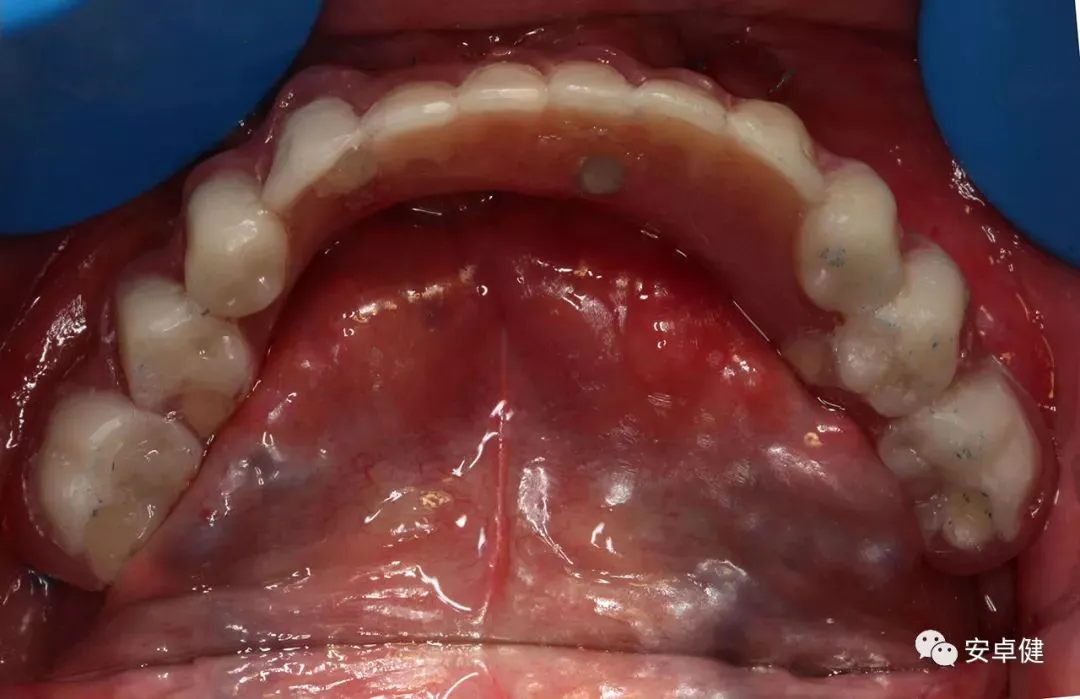

种植术前下颌合面照

种植术前拆除下颌义齿后合面照